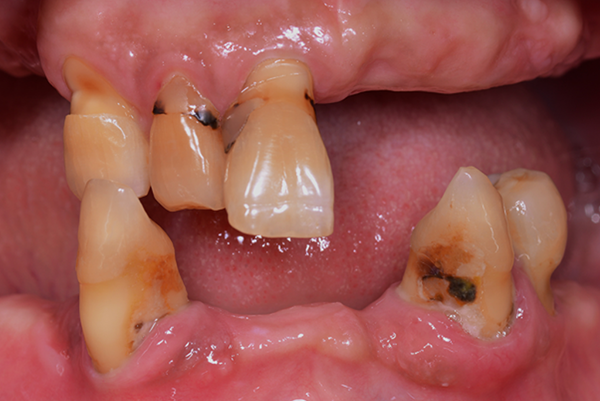

겉으로 보기에도 치석과 염증이 심하며, 잇몸이 심하게 붓고 내려앉아 있습니다. 엑스레이에서는 뿌리의 절반 이상이 드러날 정도로 잇몸뼈가 심각하게 소실되어 있습니다.